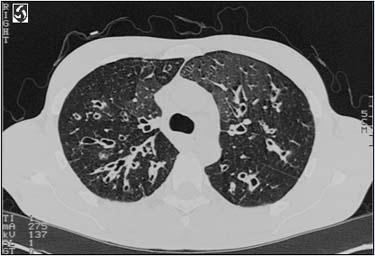

问题 患者,男性,因咳嗽、咳痰来院就诊,胸部CT如图所示,最可能的诊断是 ( )

选项 A、肺结核 B、肺癌 C、肺大疱 D、支气管扩张 E、肺炎

答案 D